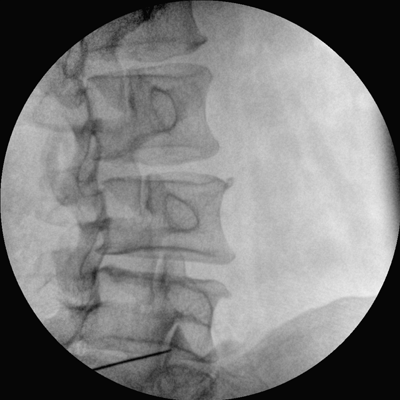

四維電動(dòng)運(yùn)動(dòng)控制,平滑定位,使得復(fù)雜角度快速實(shí)現(xiàn)。

專(zhuān)業(yè)的圖像處理系統(tǒng),為您提供高分辨率、高灰階圖像。